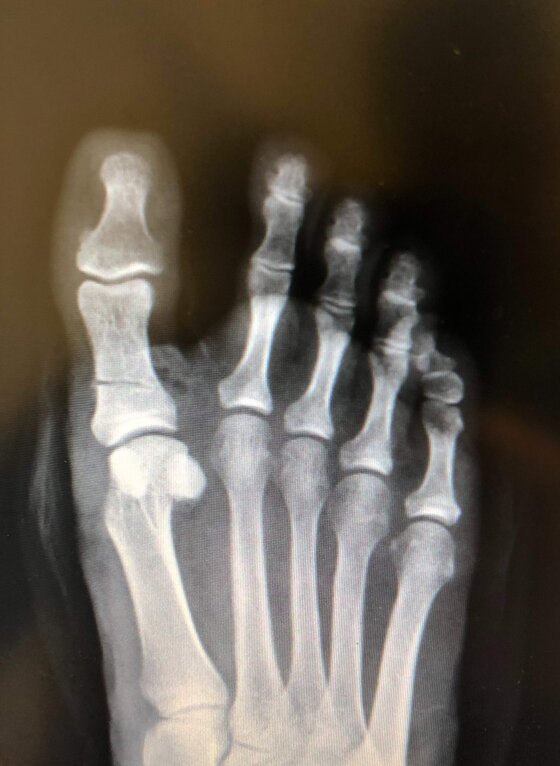

Radiografie post-operatorie in AP e LL di intervento di correzione di Alluce Valgo con tecnica mini-invasiva senza utilizzo di mezzi di sintesi metallici. Per l’osteotomia di correzione del I MT ho utilizzato un pin riassorbibile che quindi non è visulizzabile alle radiografie, mentre per l’osteotomia della prima falange del primo dito non ho utilizzato alcun mezzo di sintesi

Radiografie post-operatorie in AP di due interventi di correzione di Alluce Valgo con tecnica mini-invasiva senza utilizzo di mezzi di sintesi metallici. Per l’osteotomia di correzione del I MT ho utilizzato in entrambi i casi un pin riassorbibile che quindi non è visulizzabile alle radiografie. Nel caso a sinistra per l’osteotomia della prima falange del primo dito non ho utilizzato alcun mezzo di sintesi, nel caso a destra non ho effettuato l’osteotomia in quanto era presente un alluce valgo meno grave